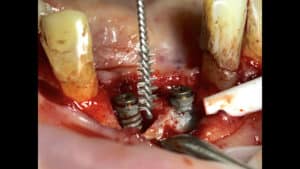

6. Ultrasonic / Piezoelectric tips

Probably the most common instrument in my protocols against mucositis and peri-implantitis. They come in many shapes and sizes, which important to adopt to the many possible anatomic configurations. The operator can control intensity and water spray, which makes it even more efficient. The rubber or plastic coating is essential when used in Mucositis or against smooth surface and prosthesis, which however inevitably limits the effectiveness and makes the tip more bulky and thus reduces accessibility. In the case of peri-implantitis treatment under flap, technically one could use a non-coated ultrasonic tip under fast water spray. In practice however this is a very unpleasant feeling for both operator and the patient, with a high pitch sound that few can withstand. The tip may easily break against metal and even if not it will wear and get inefficient very fast. So we have to stick to the coating, which however is shown to leave remnants of rubber or plastic on the rough surface. What could be the potential implications of such remnants is yet to be seen. Consequently, although I tend to use a lot the coated tips, in the case of flap surgery I use titanium brushes after the ultrasonic tip or at least finish the surgery with a “rinse and polish” ceremony as discussed at the start of this article!

7. Titanium Brushes

A later evolutionary step in implant surface decontamination, the titanium brushes were aimed at eliminating both hard and soft deposits from implant rough surface. As these brushes also remove a superficial layer of titanium from the implant surface, one could see them also as a precursor to implantoplasty. I have used two types of such brushes, one the “vertical” brush and the other being a bristle.